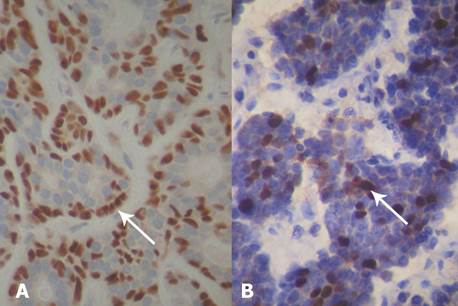

Immunohistochemical labeling was used to find the differentiation of basaloid cells in epithelial (CK 19) and myoepithelial cells (p63 and α-smooth muscle actin) (Fig. 3A). The proliferating capacity of the tumor was studied with the marker for Ki-67. A positive score was given only if there were over 10% of marked cells8: the result was 25% of positive cells. (Fig. 3B).

Primary basaloid tumors of the salivary glands are lesions characterized by a predominance of “basaloid” epithelial cells with round or ovoid nuclei surrounded by a thin cytoplasm. The term “basaloid epithelial cells” arose from observations with standard histological techniques that do not make it possible to distinguish if there are myoepithelial or ductal or basal epithelial cells. In these cases, immunohistochemical labeling is a useful tool to detect both cell types, since it improves diagnostic accuracy. The immunohistochemistry panel used in the case described (p63, α-smooth muscle actin and CK19) was important for the diagnosis of the “basaloid” cells of this carcinoma9,10.

In a previous study we obtained a negative Ki-67 labeling in the basal cell adenoma, unlike the basal cell adenocarcinoma, where we observed a proliferation index greater than 25%, which also explains the unfavorable evolution of this patient10.

Epithelial and myoepithelial cells coexist in the basal cell adenocarcinoma of the salivary glands, identified through immunohistochemical markers.

Capsular, perineural and periparotid adipose tissue invasion, Ki-67 positive immunolabeling with a proliferative index of 25% and metastasis in a regional lymphoid node and in the maxillary sinus are factors of poor prognosis that, associated with late diagnosis, explain the unfavorable evolution of the patient.